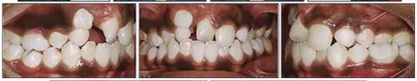

咬合關(guān)系:右側(cè)磨牙有II類關(guān)系傾向,尖牙關(guān)系II類;左側(cè)磨牙關(guān)系完全II類,尖牙關(guān)系I類。上頜雙側(cè)反合,中線稍有偏離。覆合、覆蓋減少。上頜中切牙向腭裂側(cè)旋轉(zhuǎn),上頜右側(cè)尖牙頰側(cè)異位萌出,雙側(cè)乳尖牙仍存在?;颊呱项M弓嚴重擁擠(擁擠度約10mm),下頜弓輕度擁擠4mm(擁擠度約4mm)(圖1 ;圖2)。牙周檢查良好。